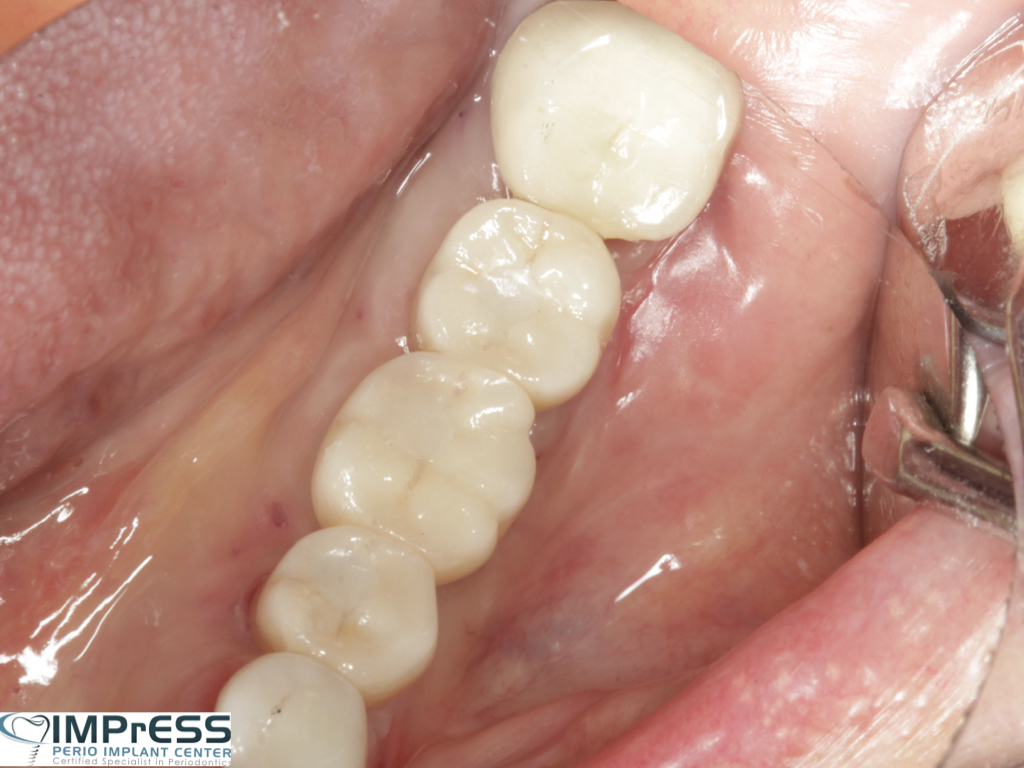

Immediate Implant Placement in Molar Extraction Site

immediate implant placement in molar site Dr. Noroozi